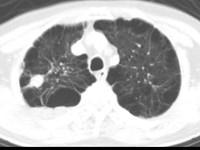

问题 男,76岁,气喘数年,胸痛1个月余,结合影像图像,选择最可能的诊断 ( )

选项 A.右上肺结核球 B.肺间质纤维化 C.右上肺瘢痕癌 D.右上肺错构瘤 E.右上肺肉瘤

答案 C